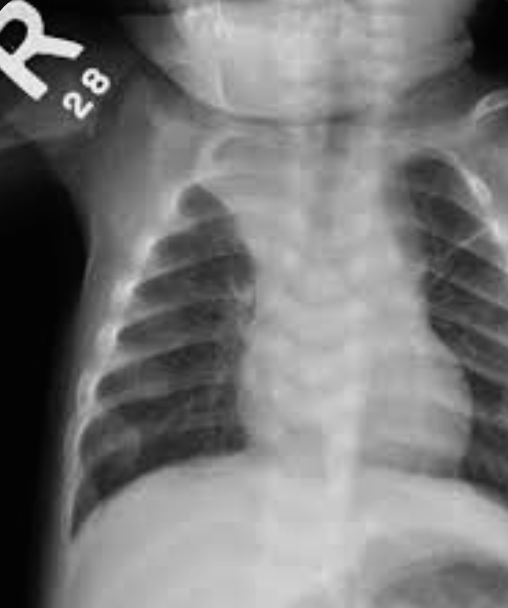

What are the X-ray findings? Widening, cupping, and fraying of metaphyseal regions, osteopenia, and widened and irregular epiphyseal plates.

Case 29: Rickets

- Rickets rosary on sides of chest X-ray may be child abuse